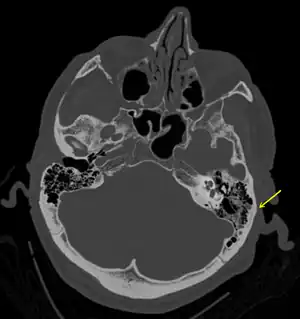

| A subtle temporal bone fracture as seen on CT in a person with a severe head injury | |